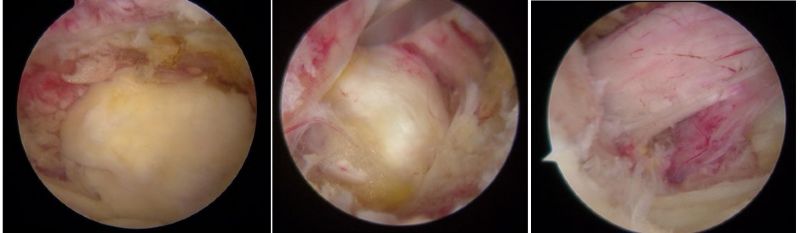

骨科內鏡下的腰椎組織

近年來,隨著脊柱內鏡技術突破性發展,以"精準減壓、最小侵襲"為核心理念的微創術式已成為60%以上腰椎手術患者的優先選擇,特別是合并多種疾病、無法耐受開放手術的高齡患者。相較于傳統開放式手術需大面積剝離肌肉組織、損傷脊柱穩定性的弊端,該技術通過直徑僅7-8毫米的骨科內鏡工作通道,在局部麻醉下借助高清內鏡可視化系統精準定位病灶,實現了"靶點精準治療"的突破性進展。